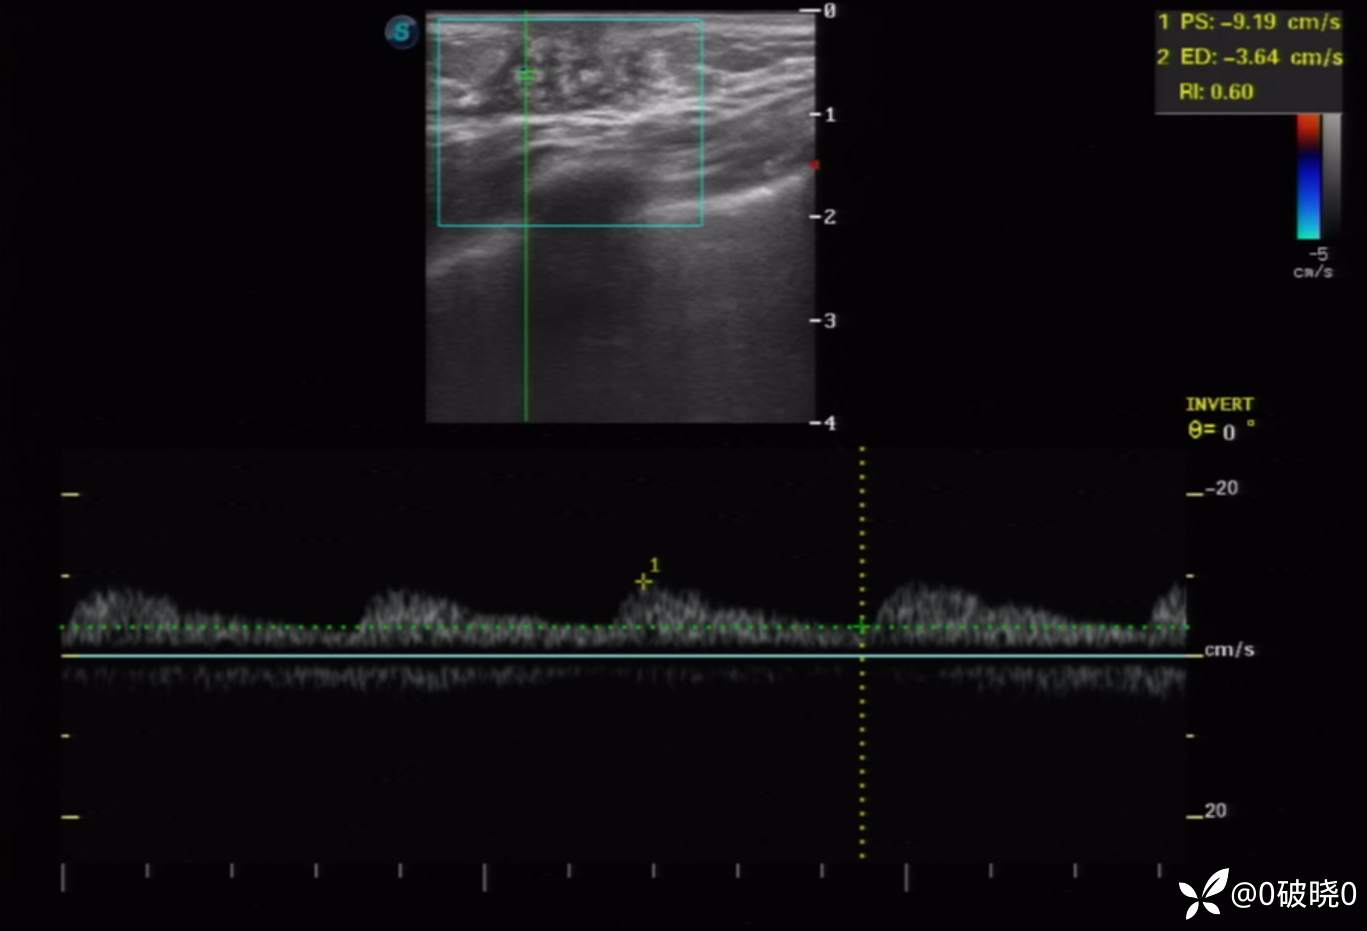

女童,7岁,9天前突感乳头处疼痛,当时家长触及到花生米大小的结节,9日后发现结节长大至2cm,但疼痛减弱,遂来诊。超声显示:包块处呈腺体样回声,其内回声不均,可见不规则低回声及团样高回声区,其旁可见细管样回声。CDFI:其内可见点、条状动脉血流信号。